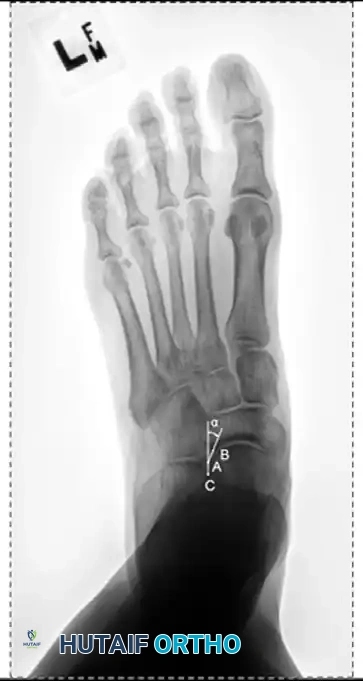

Standard evaluation requires standing AP, lateral, and mortise views of the foot and ankle.

- AP View: Assess the talonavicular coverage angle. Uncovering of the talar head indicates forefoot abduction. The talus-first metatarsal angle (normally 0 degrees) will be elevated.

- Lateral View: Assess the medial longitudinal arch.